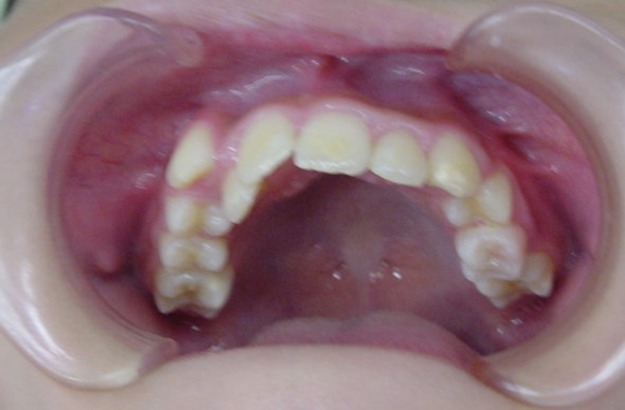

Before

| 症状 | 上顎前歯の右側転位のために、右側2番の舌側転位と右側3番(犬歯)の萌出スペースなし。 |

| 通院時の 年齢 |

10歳2か月 |

| 通院目的 | 永久歯を抜かずに治したい。右上の八重歯が気になる。 |

| 処置内容 | 1期治療 プレート拡大装置 2期治療 マルチブラケット装置(右上7番抜歯してそこに右上8番親知らずを誘導した。) |

| デメリット・院長コメント | 永久歯を抜かない治療のデメリットは、治療期間が長いことです。ただし、その後の人生の長さを考えると、健全な小臼歯を2本または4本抜歯の矯正治療よりも、はるかにメリットがあるといえます。また、アーチが小さくならないので、舌が後ろに押し込まれないためいびき防止につながり睡眠の質の向上にもつながります。 |